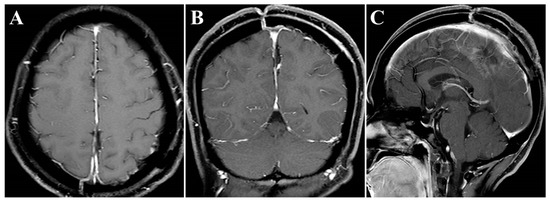

The surgery was uneventful, and the pathological diagnosis was FM, WHO grade I (Figure 3). After surgery, the patient had an uneventful recovery and was discharged with no neurological deficit. The initial clinical follow-up was performed 6 months after surgery, at which point, MRI suggested that the compressed cerebral cortex had returned to its normal form (Figure 4). After 6 months of follow-up, subsequent follow-up visits were performed at yearly intervals or more frequently when indicated. During the 24-month follow-up, the patient’s condition remained favorable, with no tumor recurrence.

Figure 4.

Postoperative contrast-enhanced MRI images. (A–C) Six months after surgery, MRI indicated regained parenchymal normal morphology. Axial (A), coronal (B), and sagittal (C) images.

Noteworthily, in this case, there were two critical draining veins above the tumor, which increased the difficulty of tumor resection. However, we successfully removed the tumor using the endoscopic ipsilateral interhemispheric approach without any venous complications during or after surgery. Additionally, the presence of ipsilateral brain edema can narrow the entry corridor, representing a key concern of the ipsilateral interhemispheric approach. However, this concern can be overcome by using the gravity-assisted technique to gain more operating space, which is sufficient to allow safe and effective removal of the tumor using the endoscopic approach [6]. In this case, the main considerations for the use of the retractor were the presence of two critical draining veins above the tumor and the absence of severe ipsilateral brain edema. Gravity-assisted lateral positioning may increase tension in the veins, leading to injury, while the retractor is more controllable to keep brain retraction to a minimum. In other situations, such as the presence of severe ipsilateral brain edema or the absence of interference of draining veins, we would implement the gravity-assisted technique to extend the lateral corridor diameters. In the current case, postoperative MRIs showed that the overlying eloquent cortex returned to its original morphology (Figure 4).